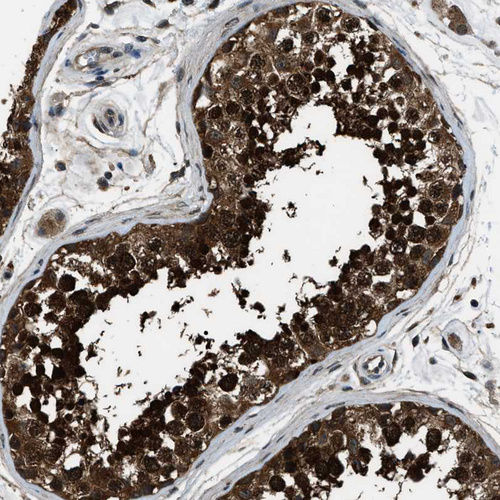

Immunohistochemical staining of human cerebral cortex, liver, lymphoid tissues and testis using Anti-NUDCD3 antibody HPA019528 (A) shows similar protein distribution across tissues to independent antibody HPA019136 (B).